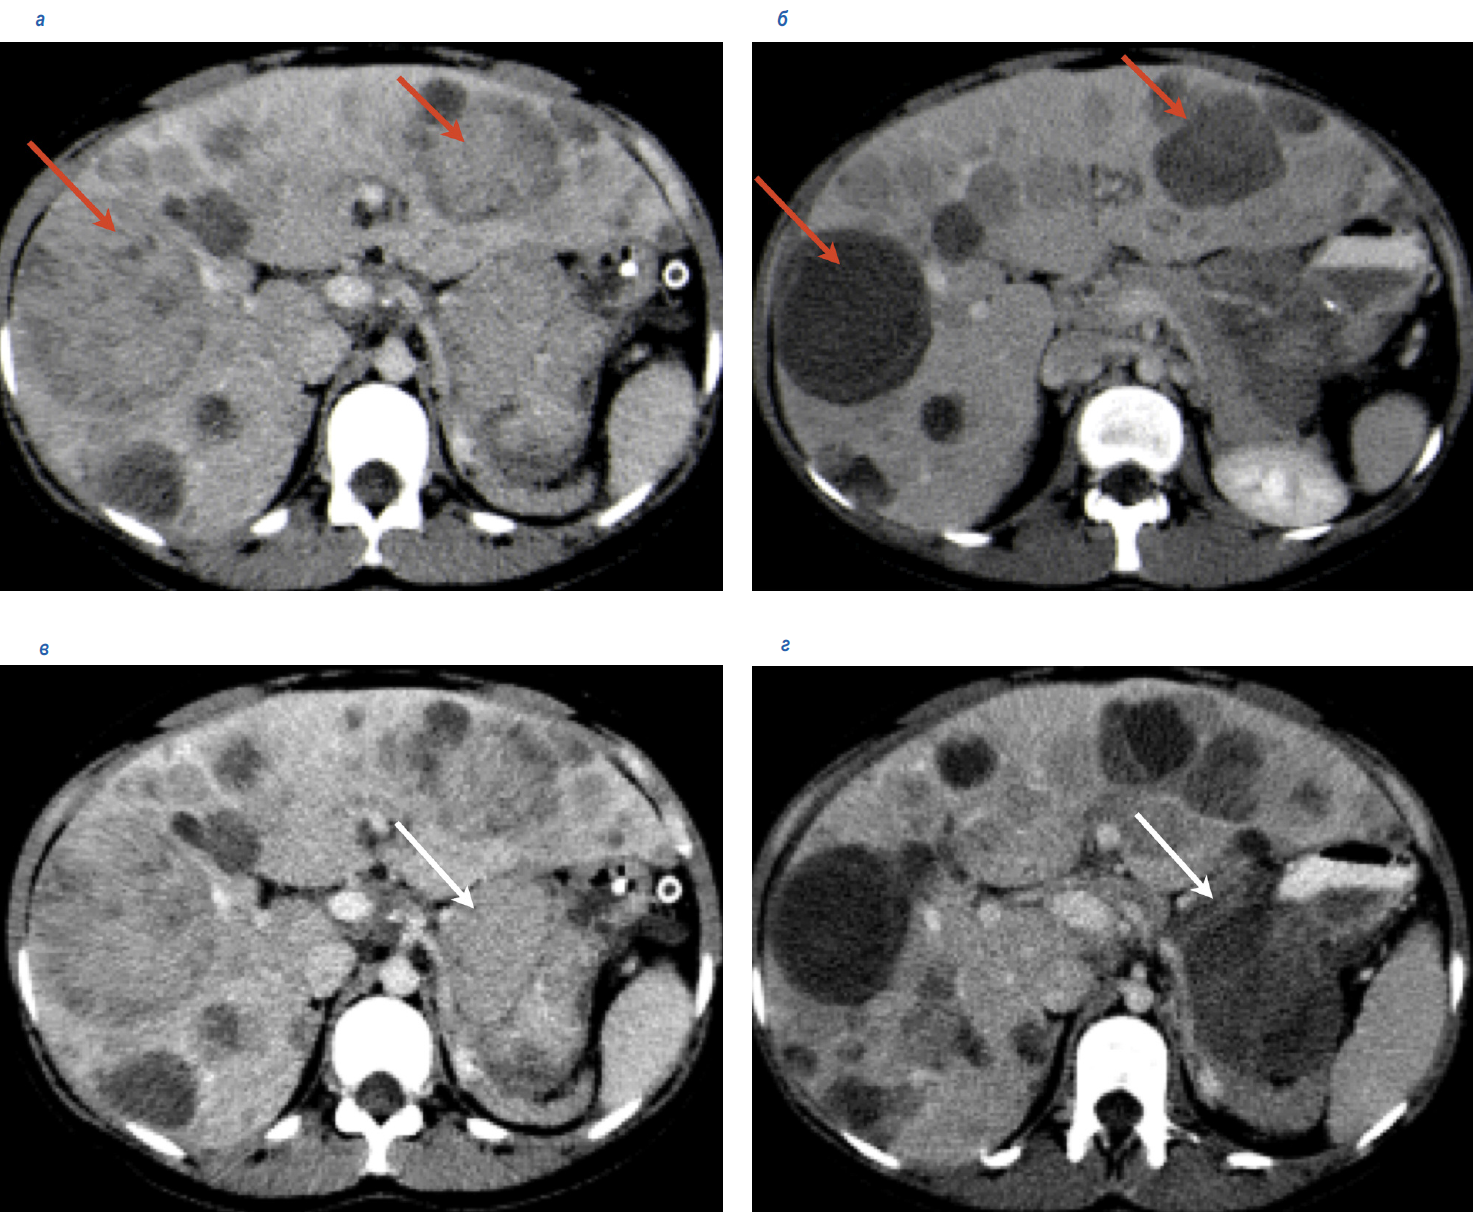

У пациентки К. 21 года при обследовании по поводу болей в правом подреберье в январе 2019 г. выявлены опухоль желудка с метастазами в печени и по брюшине, хондрома в левом легком (рис. 2). Выполнена биопсия метастаза в печени, при гистологическом исследовании – ГИСО эпителиоидноклеточного строения с положительной экспрессией CD-117. При молекулярно-генетическом исследовании мутаций генов C-KIT, PDGFRA не выявлено. При иммуногистохимическом (ИГХ) исследовании выявлен дефицит SDHB. Таким образом, у пациентки установлен диагноз неполной триады Карнея.

Рис. 2. Данные КТ до начала лечения: а – опухоль желудка (белая стрелка), а – метастазы в печени (красные стрелки); б – хондрома в левом легком (синяя стрелка).

Fig. 2. Computed tomography (CT) data before the treatment: a – the tumor of the stomach (white arrow), a – liver metastases (red arrows); b – chondroma of the left lung (blue arrow).

С января 2019 г. пациентка принимала иматиниб в дозе 400 мг/сут, который был назначен до получения результатов молекулярно-генетического и ИГХ-исследований. При повторном визите через 4 нед пациентка отметила улучшение общего состояния, в связи с чем, несмотря на полученные результаты молекулярно-генетического и ИГХ-исследований, было принято решение о продолжении терапии иматинибом. Через 2 мес терапии, в апреле 2019 г., по данным компьютерной томографии (КТ), отмечена положительная динамика – уменьшение размеров и плотности метастазов в печени и опухоли желудка (рис. 3).

Рис. 3. КТ в динамике на фоне приема иматиниба: а, в – до начала лечения, а – метастазы в печени, в – опухоль в желудке (февраль 2019 г.), б – через 2 мес терапии (апрель 2019 г.) – кистозная трансформация метастазов в печени, г – через 2 мес терапии, кистозная трансформация опухоли в желудке.

Fig. 3. Dynamic CT scanning against the background of applying imatinib: a, c – before the treatment, a – liver metastases, c – the tumor of the stomach (February 2019), b – after 2 months of therapy (April 2019) – cystic transformation of the liver metastases, d – after 2 months of therapy, cystic transformation of the tumor of the stomach.

Эффект длился с февраля по сентябрь 2019 г. При контрольном обследовании в сентябре 2019 г. выявлено прогрессирование заболевания, проявившееся ростом метастазов по брюшине в парагастральной области, при дальнейшем уменьшении метастазов в печени, уменьшении опухоли в желудке.